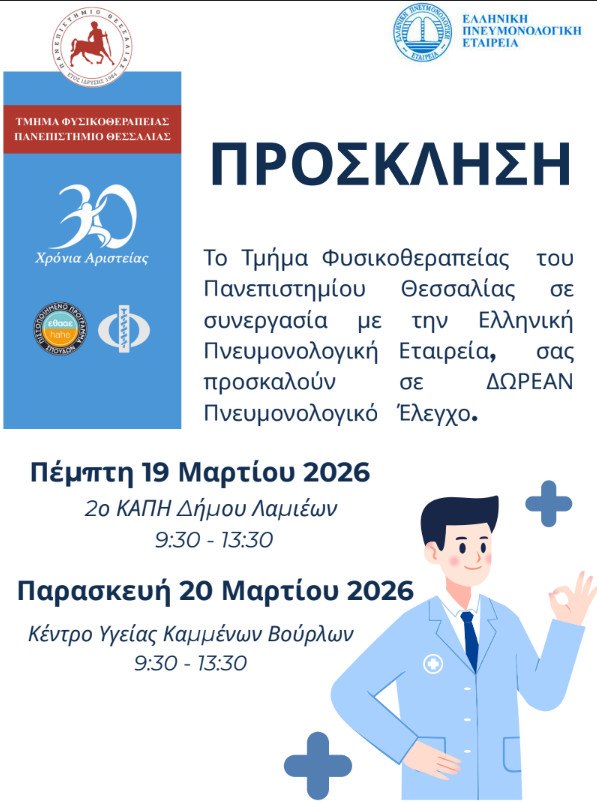

Το Τμήμα Φυσικοθεραπείας του Πανεπιστημίου Θεσσαλίας σε συνεργασία με την Ελληνική Πνευμονολογική Εταιρεία διοργανώνουν για 3η συνεχή χρονιά Έλεγχο Πνευμονικής Λειτουργίας.

Η δράση απευθύνεται σε ενήλικες (όλων των ηλικιών), είναι δωρεάν και στοχεύει στην πρόληψη και πρώιμη διάγνωση Πνευμονικών Παθήσεων.

Πέμπτη 19/3/2026: 2ο ΚΑΠΗ Δήμου Λαμιέων

Ομήρου και Αντιγόνης (Λαμία)

Από 9:30 έως 13:30

Παρασκευή 20/3/2026: Κ.Υ. Καμένων Βούρλων

Καινούργιο Φθιώτιδας

Από 9:30 έως 13:30